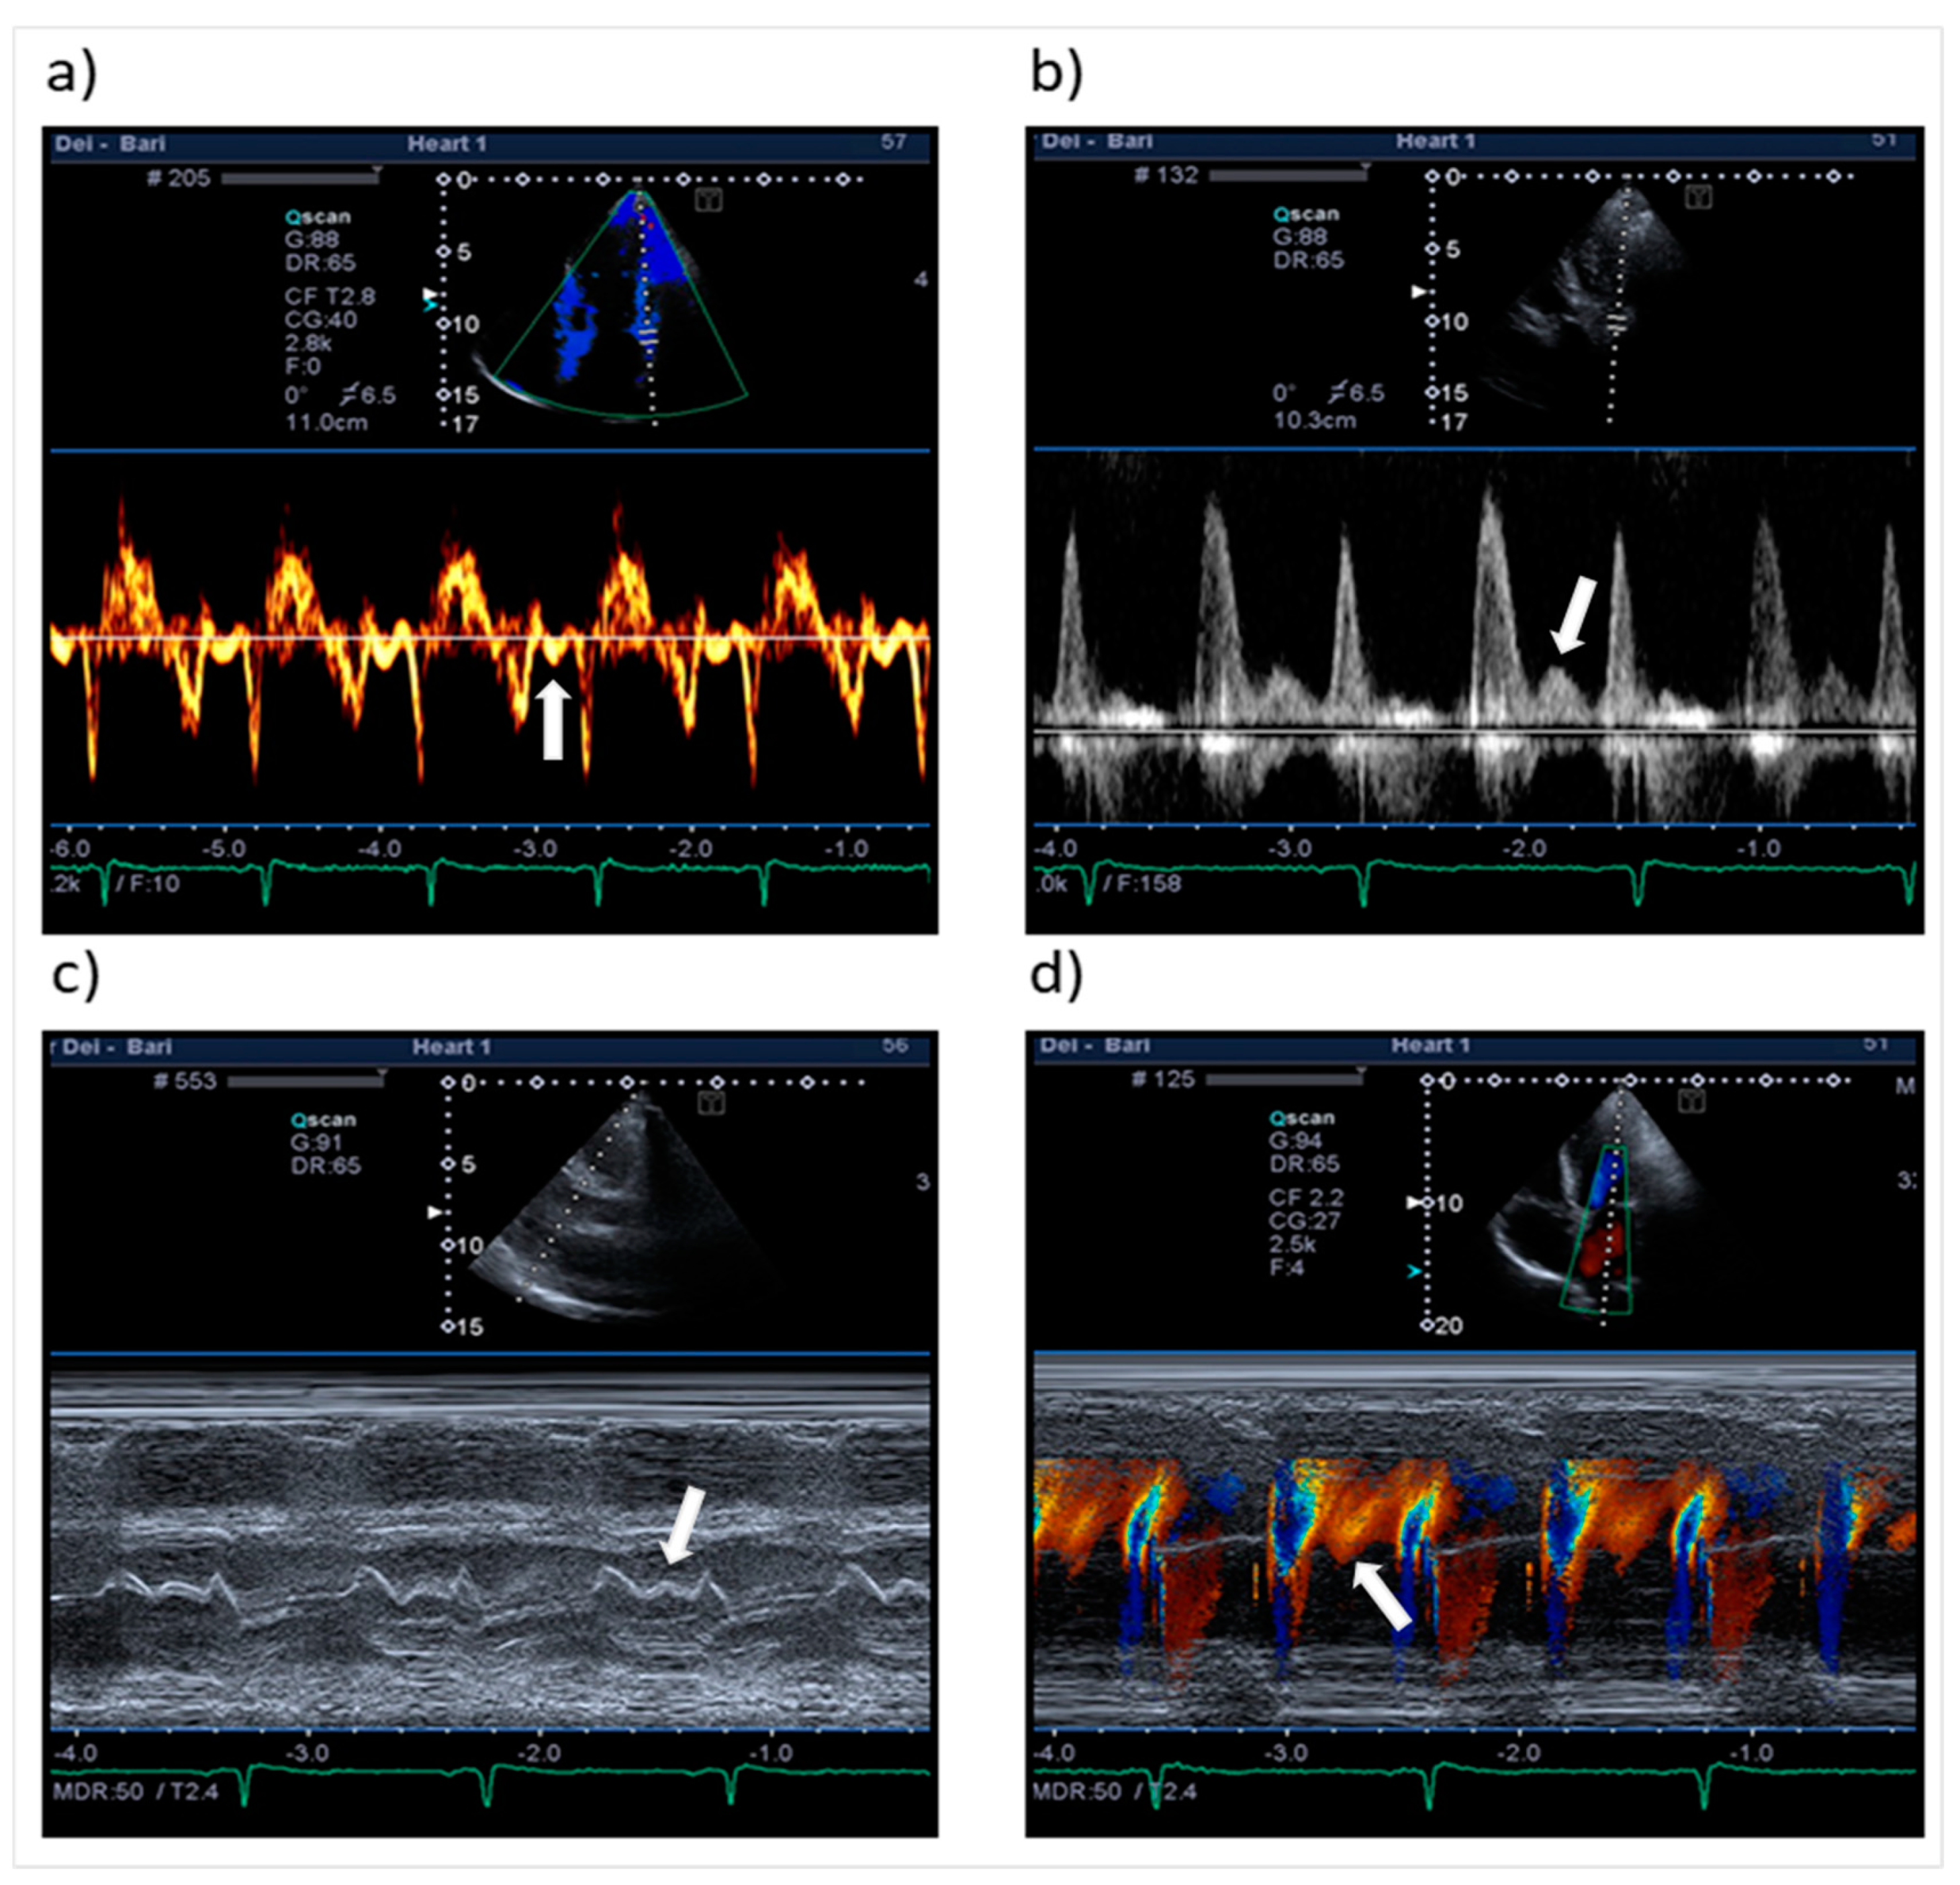

| Mid-diastolic transmitral flow velocity (L wave) | Distinct forward flow velocity after E wave with peak velocity ≥ 20 cm/s | Apical four-chamber view, sample volume at the tips of mitral leaflets with PW Doppler |

| Mid-diastolic mitral valve motion (L motion) | Mid-diastolic opening and closing motion of the mitral valve | Parasternal long-axis view M-mode along the line-cutting mitral valve |

| Mid-diastolic mitral annular velocity (L’ wave) | Distinct basilar–apical tissue velocity after E’ wave present in all cardiac cycles * | Apical four-chamber view, sample volume at septal and lateral mitral annular corners (TDI and PW Doppler) |